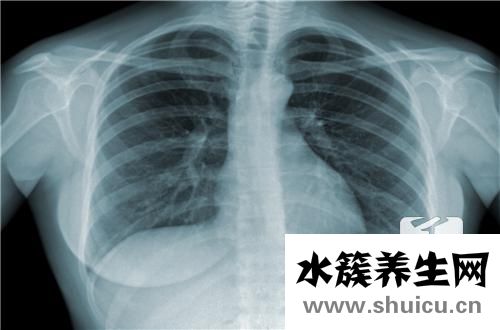

磁共振查驗時病人被放置電磁場中,接納一系列的單脈沖后,弄亂組織內(nèi)的質(zhì)子健身運動,當(dāng)單脈沖終止后質(zhì)子的電子能級和相位差修復(fù)到激起前的情況,這一全過程稱之為馳相,馳相分成豎向馳相通稱t1相,和橫著馳相通稱t2相。磁共振查驗廣泛運用于腦血管病、脫髓鞘病變病癥、腦腫瘤、腦顱先天性發(fā)育不全、顱腦外傷、各種各樣原因引發(fā)的腦部感染及其腦變性病的確診和診斷。